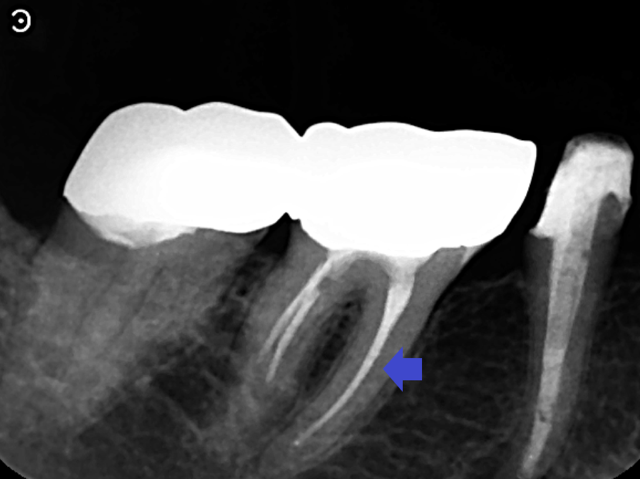

実際に「根管」の画像をご覧頂きましょう。歯の中にある黒い筋が根管です。